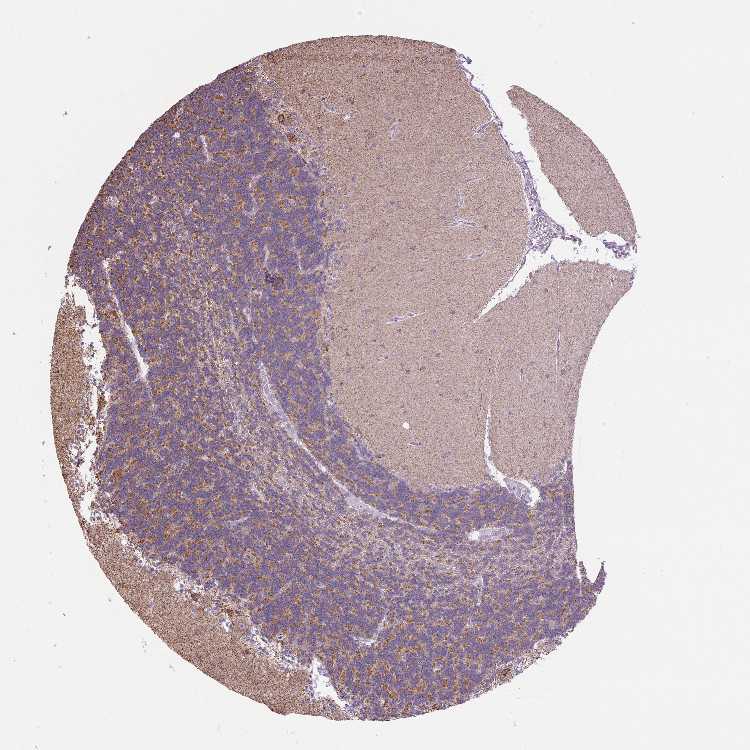

CEREBELLUM - Antibody stainingi

Antibody staining in the annotated cell types in the current human tissue is reported as not detected, low, medium, or high, based on conventional immunohistochemistry profiling in selected tissues. This score is based on the combination of the staining intensity and fraction of stained cells.

Each image is clickable and will lead to virtual microscopy that enables deeper exploration of all samples and also displays staining intensity scores, fraction scores and subcellular localization as well as patient and tissue information for each sample.

Antibody HPA056254

Purkinje cells Medium

Cells in granular layer Medium

Cells in molecular layer Medium